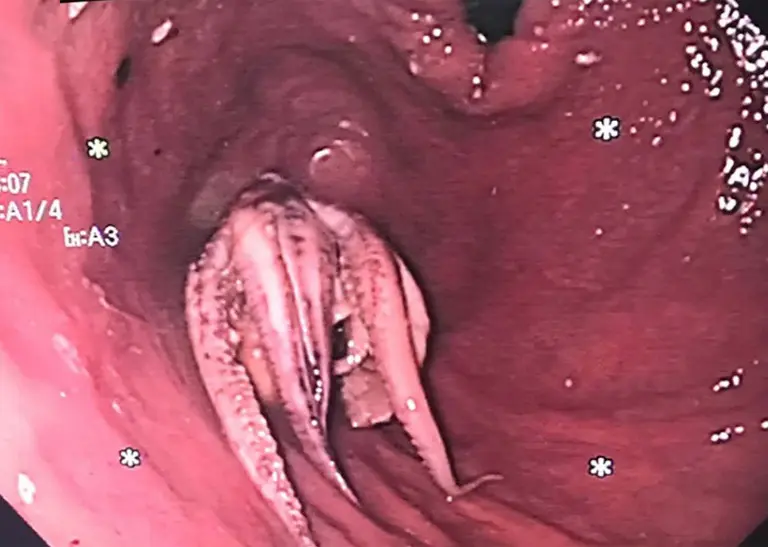

After that, the patient has an esophagogastroduodenoscopy, which is an examination of the digestive system using a small, flexible tube with a camera. This showed that the tentacled octopus was stuck 2 inches from the border between the oesophagus and the stomach.

After that, the patient has an esophagogastroduodenoscopy, which is an examination of the digestive system using a small, flexible tube with a camera. This showed that the tentacled octopus was stuck 2 inches from the border between the oesophagus and the stomach.

First efforts to push or pull out the intruder failed, so doctors used an endoscope to get around the octopus and into the stomach, where they bent it backwards. The head of the animal was then grabbed with forceps and pulled out of the person.